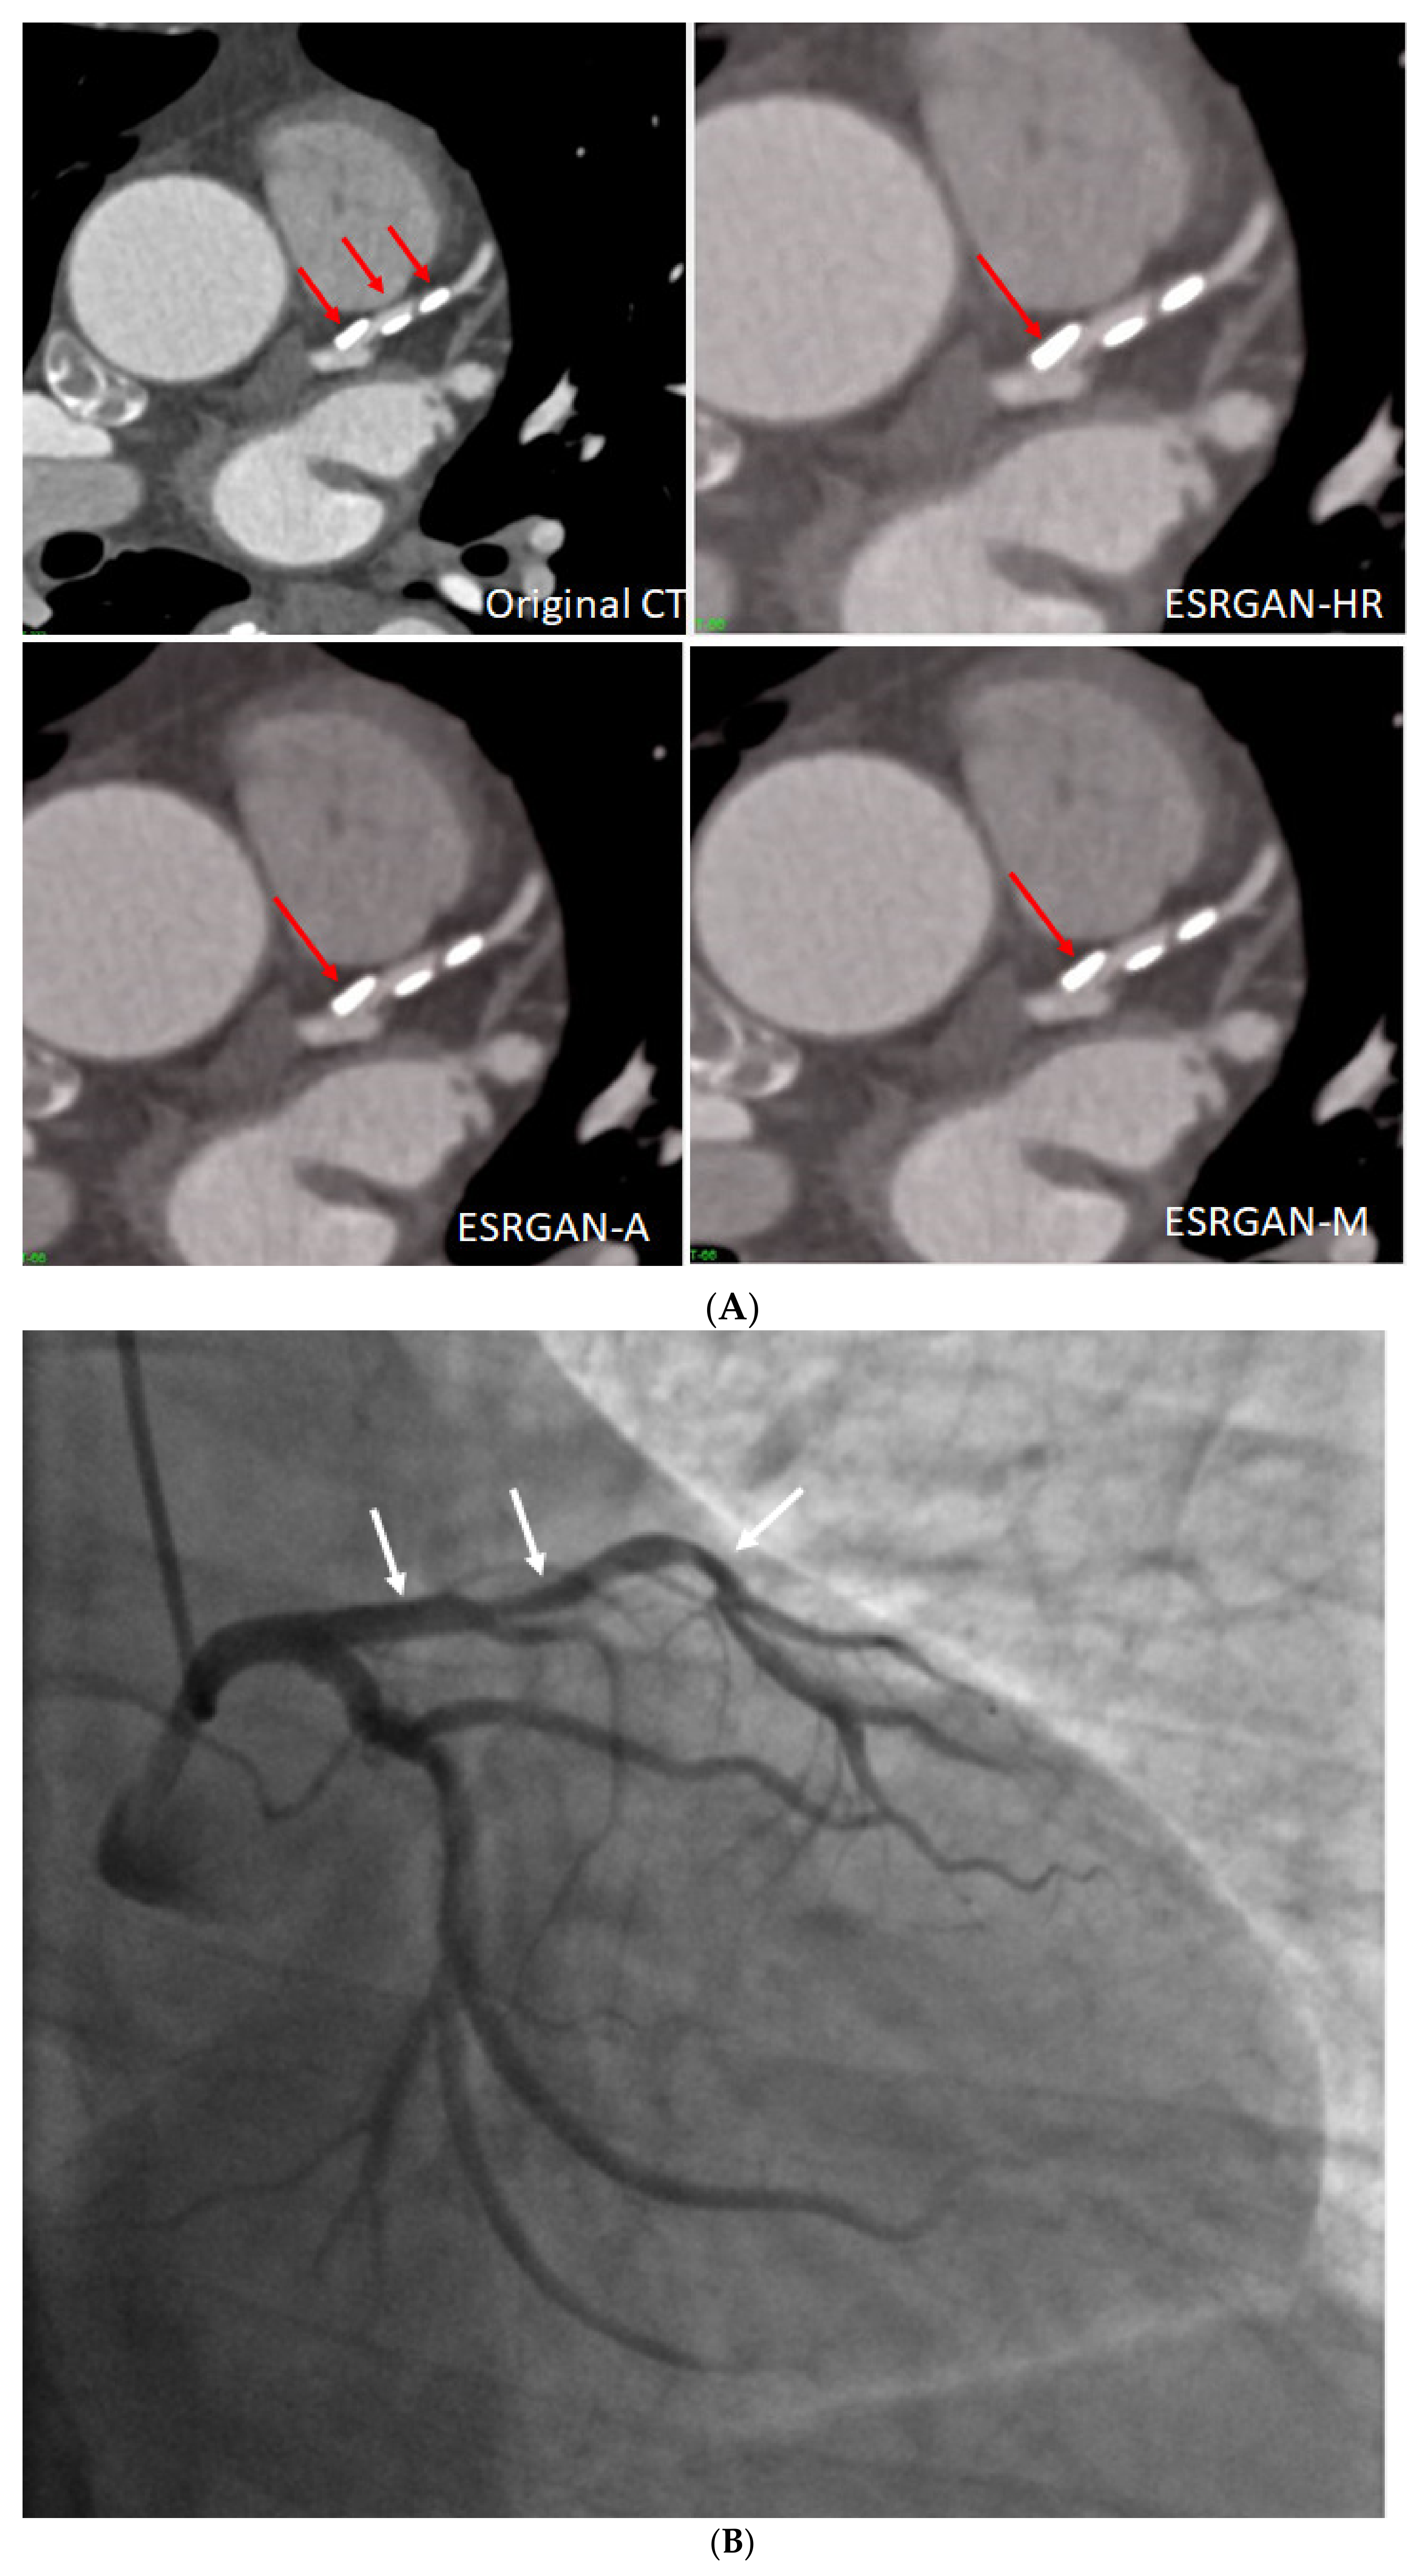

1. Introduction

2.2. Deblooming in CCTA

2.5. Reduction of Blooming Artifact by ESRGAN